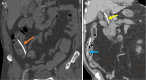

Endoscopic retrograde cholangiopancreatography (ERCP) is a cornerstone procedure for the diagnosis and management of pancreatic and hepatobiliary diseases. Although its diagnostic role has been increasingly supplanted by noninvasive imaging modalities such as magnetic resonance imaging (MRI) and magnetic resonance cholangiopancreatography, the therapeutic applications of ERCP have continued to expand. ERCP is widely used and has a generally favorable safety profile. However, it is important to recognize expected post-procedural imaging findings and serious complications that can arise. The increasing complexity of therapeutic interventions and the growing volume of procedures have led to a higher incidence of complications that often present with overlapping clinical and laboratory features, underscoring the critical role of imaging in differential diagnosis. This review focused on the typical normal ERCP findings and the imaging characteristics of common complications, including pancreatitis, bleeding, ERCP-related infections, perforations, and stent-related complications. Computed tomography (CT) is particularly valuable in timely recognition, management, and surgical decision-making for these complications. Furthermore, MRI offers a radiation-free alternative for managing complications in selected patients. Therefore, radiological modalities, particularly CT and MRI, are critical tools for the rapid diagnosis, management, and surgical decision-making processes for post-ERCP complications.